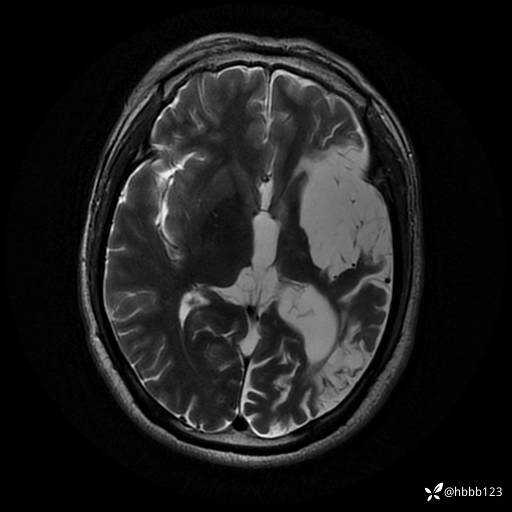

T2: